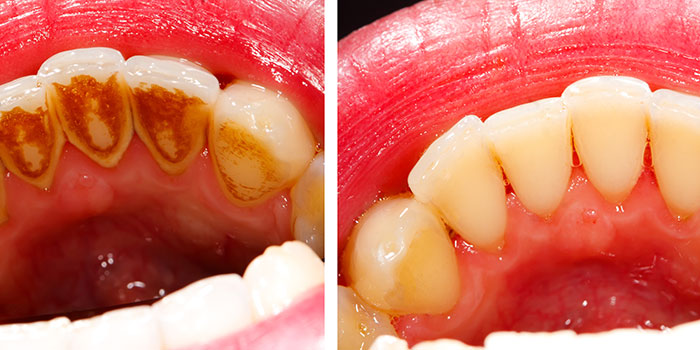

Diş tartarı temizleme, evde uygulanabilecek farklı yöntemlerle gerçekleştirilebilmektedir. Protezlerde, dişlerde ve diş eti üzerinde tutunan yumuşak ve yapışkan bir tabaka olan diş plakları; tükürük içerisinde yer alan mineraller ile birleştiklerinde sertleşerek diş tartarı denilen tabakanın oluşmasına neden olur. Tartar; dişlerde bakteri oluşumu, gıda kalıntısı birikmesi, genetik faktörler ve düzenli diş bakımı yapılmaması nedeniyle zaman içerisinde meydana gelmektedir. [caption id="attachment_6144" align="alignright" width="400"]

diş tartarı temizleme[/caption] Diş tartarı evde uygulanabilecek doğal yöntemlerle de temizlenebilmektedir. Söz doğal yöntemler ise şunlardır:

Diş Tartarı temizleme, ağız hijyeninin yeterli olmaması nedeniyle, diş ve diş etlerinde oluşan plakların temizlenmesi adına yapılan işlemdir. Diş tartarları, dişlerde sarıdan kahverengiye dönen oldukça koyu renkli yapılardır. Plaktan farklı olarak diş ipi ya da diş fırçası ile temizlenmeleri söz konusu değildir. Diş tartarı diş minesine yapışık haldedir ve bu nedenle de mutlaka diş hekiminden yardım alınması gerekir.